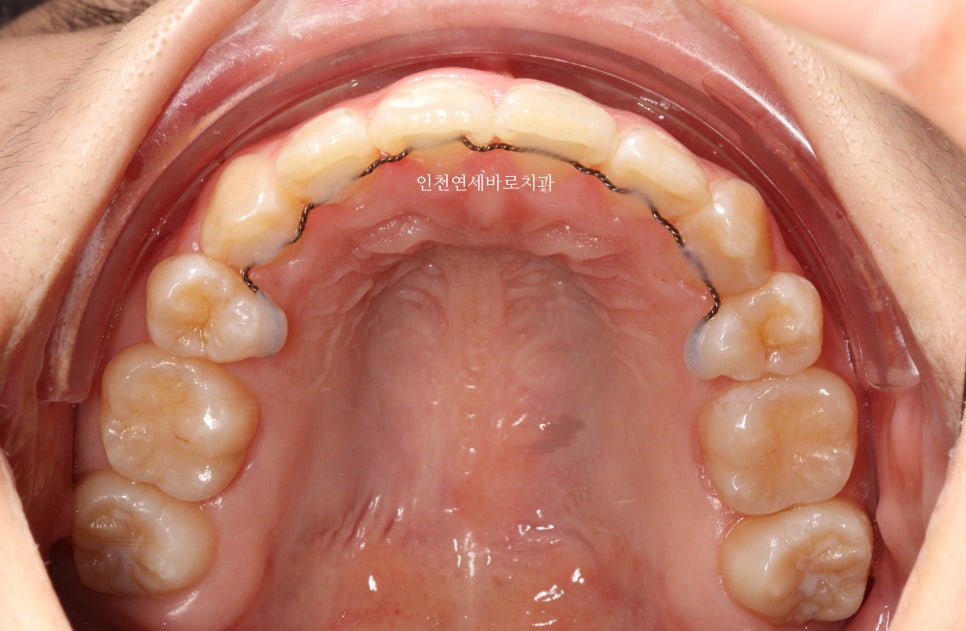

그리고 치료가 마무리 된 후의 모습입니다.

위 환자분의 재교정 치료기간은 약 7개월입니다.

7개월동안 병원은 두번 왔구요.